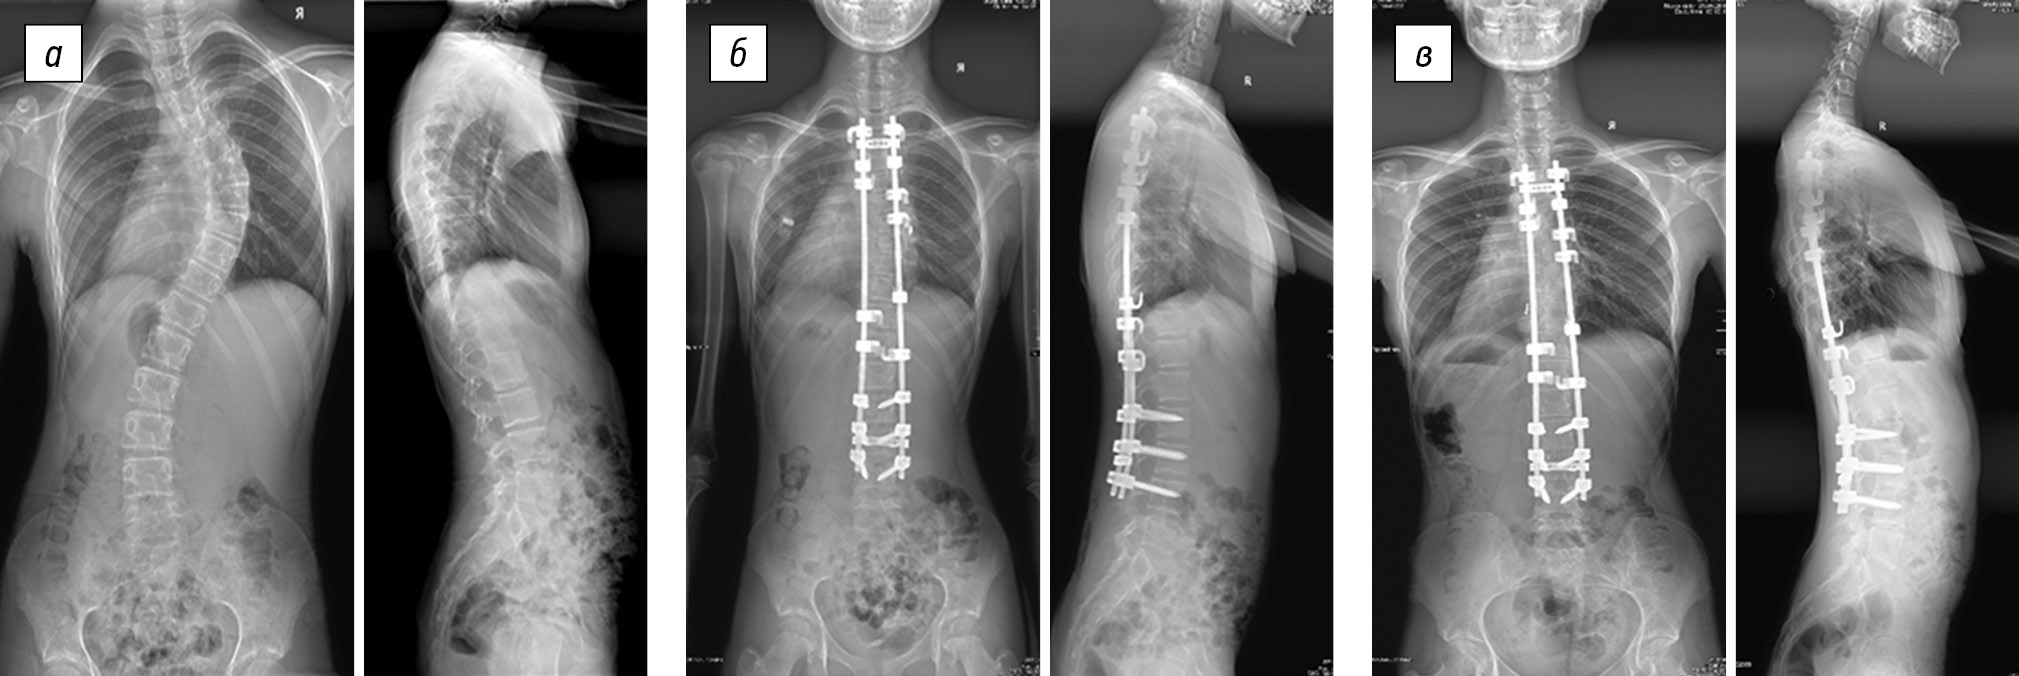

In group 2 (Table 2), the preoperative size of the thoracic scoliotic curve was 78.9 ± 19.5°, and the postoperative thoracic scoliotic curve was reduced to 25.1 ± 12.7° (p < 0.05). The value of the primary correction was 53.8 ± 13.1°, which was found in 68.7 ± 10.0% of the cases (p < 0.05). Postoperative progression was on average 1.9 ± 1.1°, which was found 3.8 ± 2.2% of the cases (Fig. 2). The average patient age was 12.1 ± 1.0 years, and the average duration of postoperative follow-up was 76.5 ± 34.5 months.

Fig. 2. Radiographs of an 11-year-old female patient in two views: a — preoperative image showing degree IV right-sided thoracic scoliotic deformity (64° according to Cobb) with lumbar anti-curvature (33°), thoracic kyphosis of 36°, and lumbar lordosis of 52°; b — surgical correction of scoliotic deformity of the spine using hybrid fixation in combination with mobilizing discectomy at the levels of Th6–Th7, Th7–Th8, Th8–Th9, and Th9–Th10 results in main thoracic curve of 21°, with complete correction of the anti-curvature curve, thoracic kyphosis of 18°, and lumbar lordosis of 33; c — X-ray control 3 years after the surgery revealed main thoracic curve of 23°, thoracic kyphosis of 18°, and lumbar lordosis of 46°

In group 4 (Table 4), the initial mean main scoliotic curve was 59.4 ± 15.0°. Primary correction was 42.1 ± 10.2°, which was found in 71.3 ± 9.2% of the cases (p < 0.05), that is, following surgery, the thoracic scoliotic curve decreased to 17.3 ± 8.2° (p < 0.05). During postoperative follow-up, patients experienced progression of the main scoliotic curve, which was 13.3 ± 7.4°, and found in 32.1 ± 16.6% of the cases (Fig. 4). The average patient age was 13.1 ± 0.8 years, and the average duration of postoperative follow-up was 154.9 ± 77.1 months.

Fig. 4. Radiographs of an 11-year-old female patient in two views: a — preoperative image of degree IV right-sided thoracic scoliotic deformity (42° according to Cobb), with thoracic kyphosis of 25° and lumbar lordosis of 60°; b — surgical correction of scoliotic deformity of the spine using laminar fixation without ventral intervention resulted in the main thoracic curve of 12°, thoracic kyphosis of 13°, and lumbar lordosis of 48°; c — X-ray control 1 year after the surgery revealed the main thoracic curve of 46°, thoracic kyphosis of 21°, and lumbar lordosis of 54°